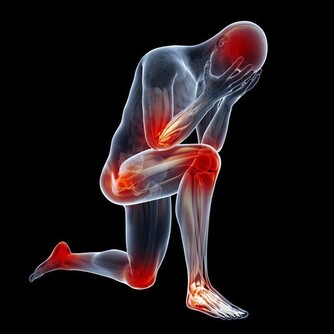

現代人長時間使用電腦、手機,或是維持不良姿勢,導致肩膀與頸部痠痛的問題越來越普遍。這種疼痛不僅影響日常生活,還可能導致長期的不適,甚至發展成慢性疼痛。本文將詳細探討肩膀與頸部痠痛的主要原因,並提供有效的預防與治療方法,幫助您改善不適,維持健康的身體狀態。

肩膀與頸部痠痛的常見原因

1. 長時間維持不良姿勢

長時間維持不正確的姿勢,如低頭滑手機、久坐不動、彎腰駝背等,會讓肩頸肌肉長時間處於緊繃狀態,造成痠痛。例如,辦公族長時間使用電腦,若螢幕高度不適當,容易導致肩頸前傾,增加肌肉負擔,導致疼痛。

2. 肌肉過度使用

重複性使用肩膀與頸部肌肉,如搬重物、頻繁低頭看手機、長時間打字等,會讓肌肉持續處於緊繃狀態,容易產生發炎與痠痛感。運動不足的人也可能因為缺乏肌力支撐,使肩頸肌肉更容易受傷。

3. 壓力與情緒緊張

壓力過大或情緒焦慮時,身體會不自覺繃緊,尤其是肩頸部位。長期處於壓力狀態,會讓肌肉過度收縮,血液循環變差,進而引發疼痛。